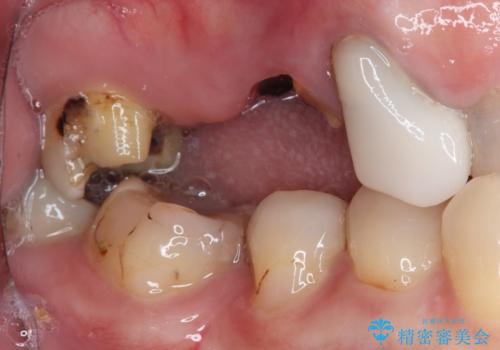

- 欠損や破折により失われた奥歯に、インプラント治療を希望して来院された患者様です。

欠損部はすぐにインプラント埋入が可能で、手前の歯根が残存している部位も、できれば抜歯をして奥と一緒に埋入をしたいところでしたが、破折による炎症が大きいため、2回に分けてインプラント埋入を行うこととしました。